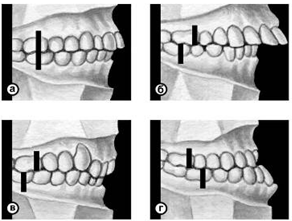

Существует множество классификаций аномалий П., однако общепринятой является международная классификация, предложенная в 1899 г. Энглом (Е.Н. Angle). В ее основе лежит соотношение первых моляров, что, по мнению Энгла, служит ключом окклюзии. В соответствии с классификацией к первому классу (рис. 6, а) относятся все аномалии, при которых первые моляры находятся в правильном соотношении (мезиально-шеечный бугор первого моляра верхней челюсти располагается в межбугорковой фиссуре первого моляра нижней челюсти), а все аномалии П. обусловлены изменениями зубов или челюстей спереди от первых моляров, например при скученности резцов, их протрузии (наклоне в сторону преддверия рта) или ретрузии (наклоне в сторону полости рта).

Во второй класс включены аномалии, при которых нарушено смыкание первых моляров и фронтальной группы зубов. Межбугорковая фиссура первого моляра нижней челюсти располагается позади мезиально-щечного бугра первого моляра верхней челюсти, т.е. нарушено смыкание зубов в сагиттальной плоскости (переднезаднем направлении). Подобные нарушения (так называемый дистальный прикус) могут быть обусловлены чрезмерным ростом верхней челюсти (прогнатией) или (реже) недоразвитием нижней челюсти (микрогенией). В зависимости от положения и смыкания фронтальной группы зубов во втором классе выделяют два подкласса: первый характеризуется протрузией резцов (рис. 6, б), второй — их ретрузией (рис. 6, в).

Третий класс (рис. 6, г) включает аномалии П., при которых межбугорковая фиссура первого моляра нижней челюсти располагается впереди мезиально-щечного бугра одноименного моляра верхней челюсти (мезиальный П., прогения, прогенический П., антериальный П.).

Рис. 6. Схематическое изображение челюстей при сагиттальных аномалиях прикуса, по классификации Энгла: а — аномалии первого класса; б — аномалии второго класса, первого подкласса; в — аномалии второго класса, второго подкласса; г — аномалии третьего класса; вертикальными линиями указано соотношение верхнего и нижнего первых моляров.